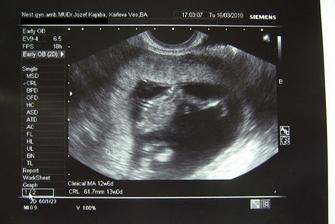

♥ 23.02.2010 sme boli zase na kontrole a všetko bolo chválabohu v poriadku. Dostali sme vytúženú knižku a aj prenatal box. Na ďalšiu kontrolu ideme o 3 dlhé týždne, dovtedy nás čaká zubárka, praktická lekárka a hematológia. Po ďalšej kontrole pôjdeme do rizikovej poradne. Už máme predbežne vybranú pôrodnicu, ale keď nastanú problémy bude sa meniť. Zistila som, že mám toho najlepšieho doktora pod slnkom - hotového anjela.